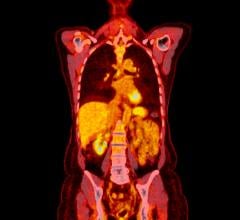

August 3, 2018 — Researchers have discovered a new nuclear medicine test that could improve care of patients with type 1 diabetes. The new positron emission tomography (PET) imaging method could measure beta-cell mass, which would greatly enhance the ability to monitor and guide diabetes therapies. This study is reported in the featured article of the month in The Journal of Nuclear Medicine’s August issue.

Beta cells and neurological tissues have common cellular receptors and transporters, so the Yale researchers screened brain radioligands for their ability to identify beta cells. Then, 12 healthy control subjects and two subjects with type 1 diabetes mellitus underwent dynamic PET/CT scans with six tracers.

The dopamine type 2/type 3 (D2/D3)-receptor agonist radioligand carbon-11 (11C)-(+)-4-propyl-9-hydroxynaphthoxazine (PHNO) was the only radioligand to demonstrate sustained uptake in the pancreas with high contrast versus abdominal organs such as the kidneys, liver, and spleen.

The results provide preliminary evidence that 11C-(+)-PHNO is a potential marker of beta-cell mass with 2:1 binding of D3 receptors over D2 receptors. While further research is needed before clinical application, 11C-(+)-PHNO is a promising way to differentiate the beta-cell mass of healthy individuals from those with type 1 diabetes mellitus, as well as track and guide therapies for diabetes patients.